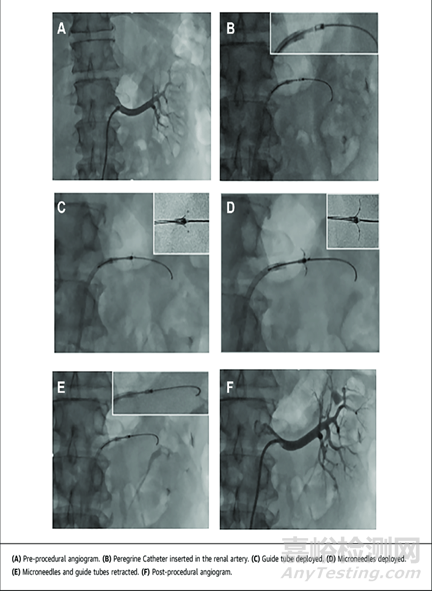

血管造影圖像

Peregrine System Infusion Catheter遠(yuǎn)端

Peregrine System Infusion Catheter的遠(yuǎn)端具有三個(gè)微型注射針,可進(jìn)行靶向注射藥物。通過類似于冠狀動脈或外周導(dǎo)管插入術(shù)的技術(shù)將Peregrine Catheter通過股動脈輸送至腎動脈。在腎動脈輸送過程中,微型注射針預(yù)先回縮至不透射線的導(dǎo)管內(nèi),從而能夠?qū)?dǎo)管安全輸送至病患處。一旦輸送到位,同時(shí)將三個(gè)微型注射針從導(dǎo)管釋放出來,以將治療藥物直接控制遞送到血管周圍空間

Peregrine System Infusion Catheter遠(yuǎn)端血管作用細(xì)節(jié)

Peregrine System Infusion Catheter使用方法

Ablative Solutions 公司旗下的Peregrine微注射導(dǎo)管消融系統(tǒng)通過股動脈進(jìn)入腎動脈,通過導(dǎo)管末端的三根微針向腎動脈外膜注射 0.3~0.6ml 的 96-98%脫水乙醇,以損傷血管外神經(jīng)的方式實(shí)現(xiàn)去腎交感神經(jīng)支配。其注射導(dǎo)管的安全性與有效性試驗(yàn)自 2014年7月起,2017年9月結(jié)束,并且被美國FDA 批準(zhǔn)用于向外周血管周圍輸注診斷和治療藥物,已于2015年5月獲得CE認(rèn)證用于進(jìn)行腎動脈神經(jīng)消融治療難治性高血壓患者。目前運(yùn)用于治療高血壓的Peregrine System 有兩項(xiàng)試驗(yàn)在進(jìn)行中,TARGET BP OFF-MED臨床試驗(yàn)和 TARGET BP I 臨床試驗(yàn)均在美國和歐洲進(jìn)行。TARGET BP I 臨床試驗(yàn)正在積極招募患者。由于化學(xué)消融包括無水酒精尚未在腎臟系統(tǒng)有過治療其他任何疾病的先前案例,因此FDA對這一器械有著額外的臨床安全性的證據(jù)要求,需要有數(shù)百例額外患者隨訪較長時(shí)間以證明其安全性。